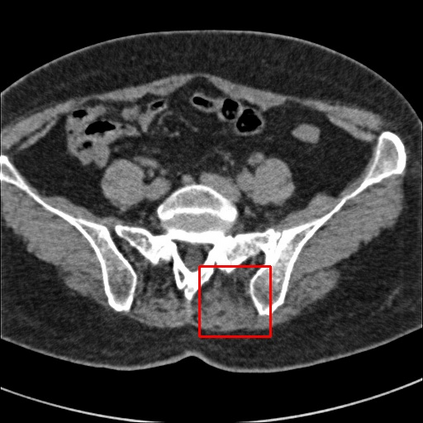

Low-Dose Computed Tomography (LDCT) technique, which reduces the radiation harm to human bodies, is now attracting increasing interest in the medical imaging field. As the image quality is degraded by low dose radiation, LDCT exams require specialized reconstruction methods or denoising algorithms. However, most of the recent effective methods overlook the inner-structure of the original projection data (sinogram) which limits their denoising ability. The inner-structure of the sinogram represents special characteristics of the data in the sinogram domain. By maintaining this structure while denoising, the noise can be obviously restrained. Therefore, we propose an LDCT denoising network namely Sinogram Inner-Structure Transformer (SIST) to reduce the noise by utilizing the inner-structure in the sinogram domain. Specifically, we study the CT imaging mechanism and statistical characteristics of sinogram to design the sinogram inner-structure loss including the global and local inner-structure for restoring high-quality CT images. Besides, we propose a sinogram transformer module to better extract sinogram features. The transformer architecture using a self-attention mechanism can exploit interrelations between projections of different view angles, which achieves an outstanding performance in sinogram denoising. Furthermore, in order to improve the performance in the image domain, we propose the image reconstruction module to complementarily denoise both in the sinogram and image domain.